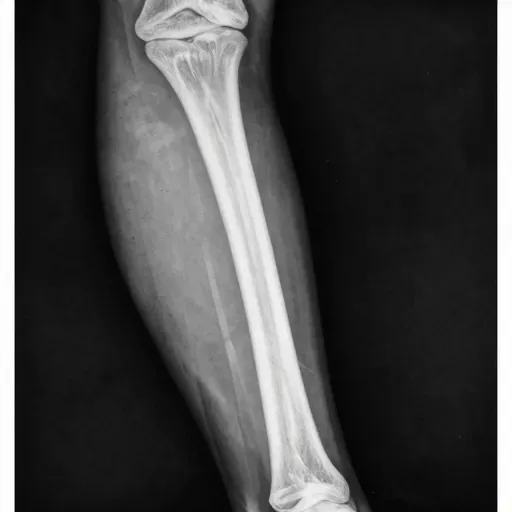

Hình ảnh:

医生通过X光照片确诊是骨折。

Bác sĩ thông qua phim chụp X-quang chẩn đoán xác định là gãy xương.